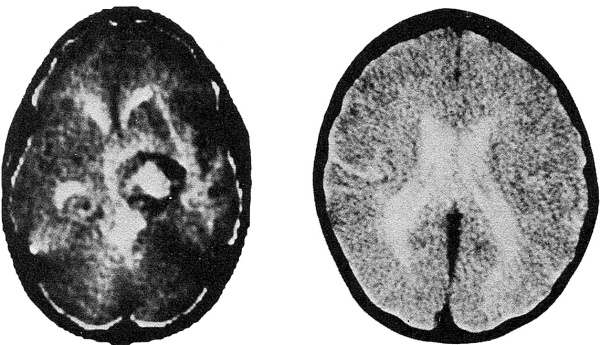

слева – февраль 1979, справа – февраль 1980

Это снимки поперечного сечения всей головы, черепа и мозга. Много-много снимков каждой части головы. На этих фотографиях показаны томографические снимки, сделанные, когда у меня обнаружили опухоль – и когда она исчезла. На самом деле это не страшно. Сначала мне все объяснили. Все, что должно происходить. Кроме того, там есть радиосвязь, и ты можешь разговаривать с врачом или попросить о чем-нибудь, если понадобится. Конечно, я ненавижу уколы. Не то, чтобы я их совсем не мог перенести, но я не могу сказать, что они мне доставляют удовольствие. Я их побаиваюсь. Ха! Да, так и знайте: я их боюсь.